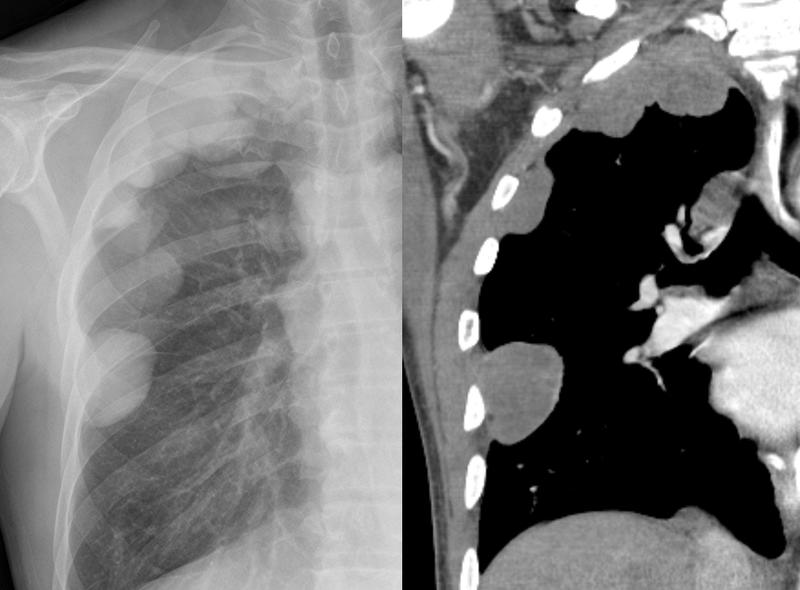

Gallery Pleural Mesothelioma

Mesothelioma